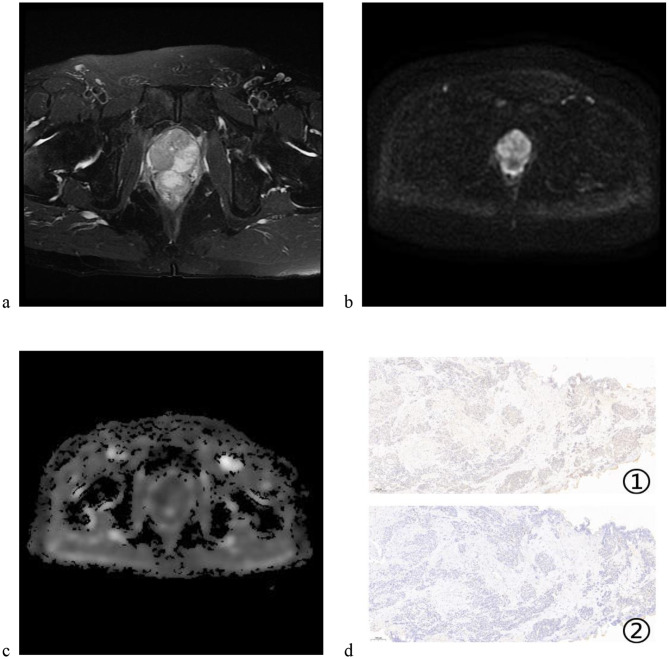

Methods: This single-center, retrospective cohort study analyzed PCa patients diagnosed between 2019 and 2022. This study employed a comprehensive interdisciplinary approach, integrating CD3+/CD8 + T cell immunoanalysis with Multiparametric Magnetic Resonance Imaging (mpMRI) analysis, while adhering to a robust multi-phase feature selection process. This included the Akaike Information Criterion (AIC), Maximum Relevance Minimum Redundancy (mRMR), and Least Absolute Shrinkage and Selection Operator (LASSO) algorithms, validated through 10-fold cross-validation. Logistic regression models were constructed for radiomic, immunologic, and combined RDIS models, with predictive performance rigorously evaluated using Receiver Operating Characteristic (ROC) curve analysis, calibration curve assessments, and Decision Curve Analysis (DCA).

Results: The RDIS model achieved an Area Under the Curve (AUC) of 0.874 in the validation cohort, outperforming traditional single-omics models, including the radiomic model (AUC: 0.844) and the immunologic model (AUC: 0.767), supporting potential use in early intervention decision-making. The correlation heatmap reveals weak to moderate correlations among 7 pairs of radiomic and immunologic features associated with PCa progression. The RDIS model demonstrates good specificity in further predicting bone metastases and castration-resistant prostate cancer (CRPC).